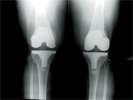

Post Op

X-Rays

Progress

Good relief of elbow pain and excellent function

Result